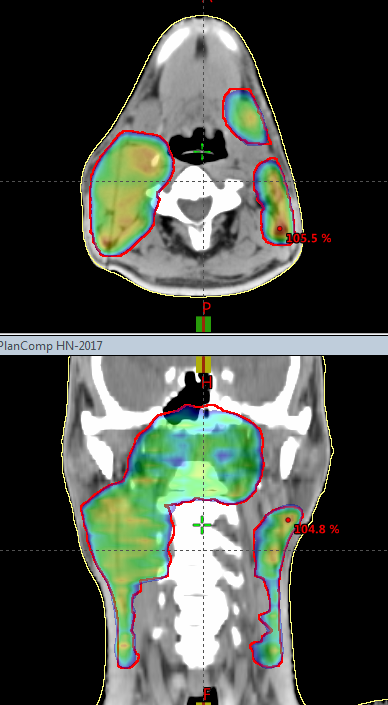

Friedemann Herberth

Score: 99.3/ 100

Hospital: Kantonsspital St.Gallen

Technique: VMAT

Rank: Second Top (Eclipse)

Job Title: Medical Engineer